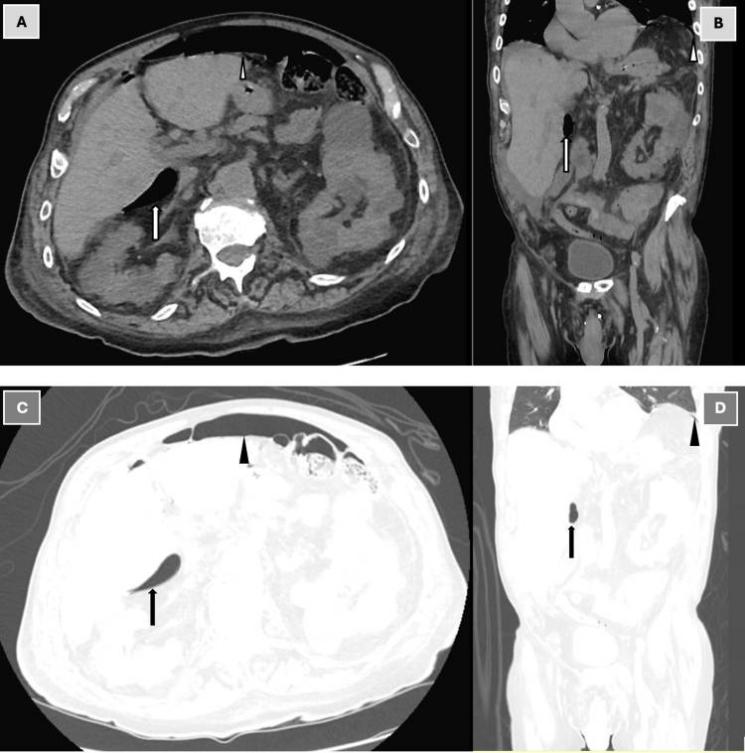

进行了肾脏、输尿管和膀胱扫描,结果显示肠型正常,但腹部和盆腔平扫CT结果令人意外:CT显示,,小网膜囊内十二指肠周围有游离气体(“气腹”),腹水,双侧少量胸腔积液,下肺叶有肺不张改变,考虑十二指肠溃疡穿孔(图1)。

图1. 腹部和骨盆CT平扫:软组织窗轴位视图(A)、软组织窗冠状位视图(B)、肺窗轴位视图(C)和肺窗冠状位视图(D)